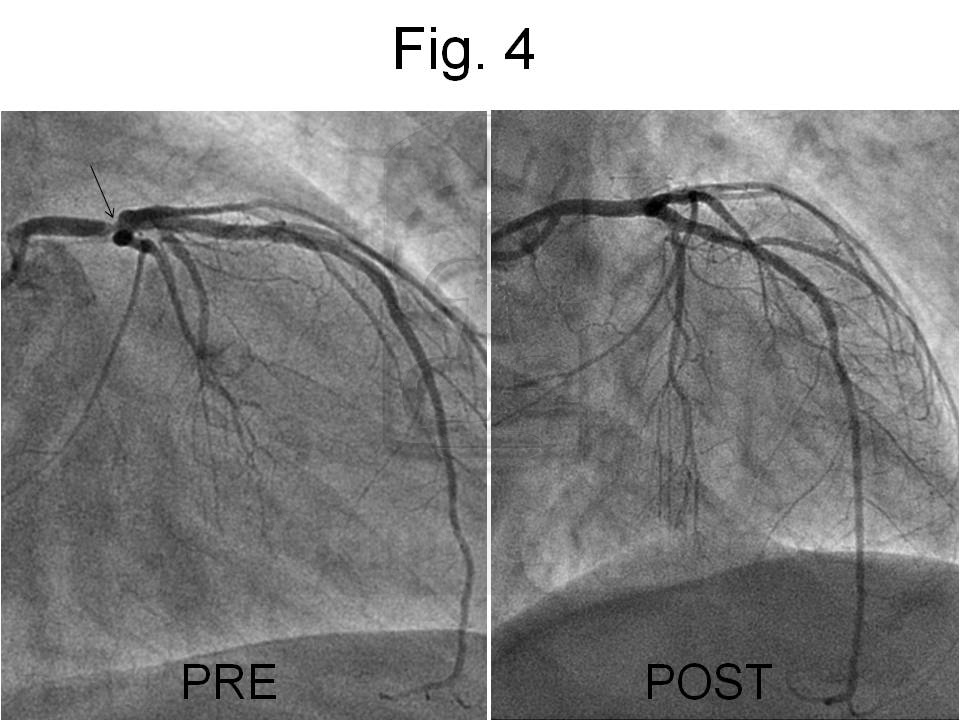

Para descartar causa isquémica, se decidió angiografía coronaria, con la sospecha de progresión de enfermedad. En la coronariografía se observó una buena evolución del stent implantado en Descendente Anterior 2 años antes, así como una progresión de enfermedad focal con lesión severa del tronco coronario izquierdo distal, afectando a una trifurcación (descendente anterior, ramo mediano y circunfleja).

La coronaria derecha no presentaba lesiones. Se cruzaron 3 guías metálicas y se implantó un stent farmacoactivo orientado hacia la descendente anterior. Se observó un buen resultado angiográfico sin afectación de los orificios implicados.

La siguiente figura muestra la imagen comparativa de la coronaria izquierda antes y después del tratamiento.